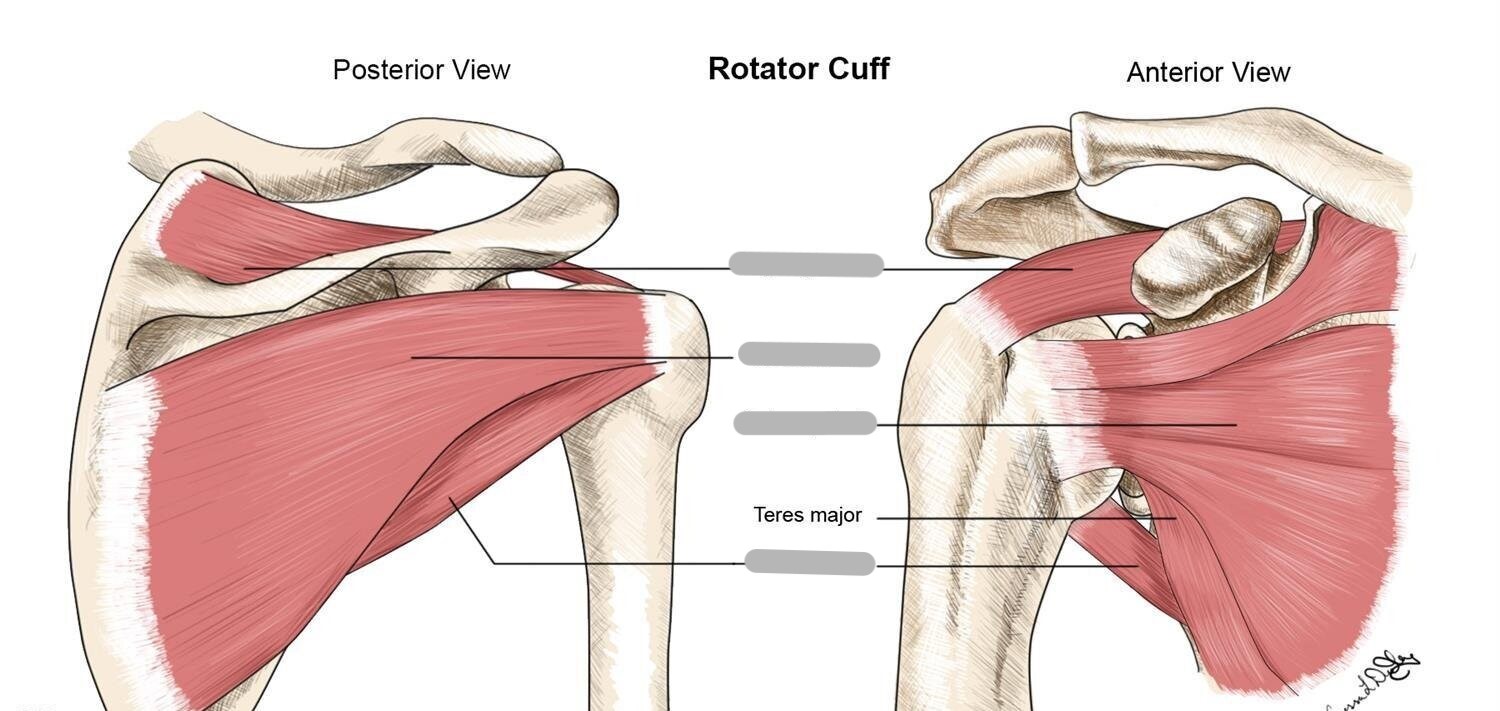

What is the rotator cuff?

group of muscles that stabilize the shoulder joint by pulling the humeral head into the glenoid fossa

What 4 muscles make up the rotator cuff?

supraspinatus, infraspinatus, subscapularis, and teres minor

Explain the location and function of the supraspinatus muscle

originates on the upper border of the posterior scapula

allows for abduction

Explain the location and function of the subscapularis muscle

originates on the anterior surface of the scapula

allows for internal rotation

Explain the location and function of the infraspinatus muscle

originates on the posterior inferior aspect of the scapula

allows for external rotation

Explain the location and function of the teres minor muscle

originates on the posterior lateral scapular border

allows for external rotation

Label the muscles of the rotator cuff